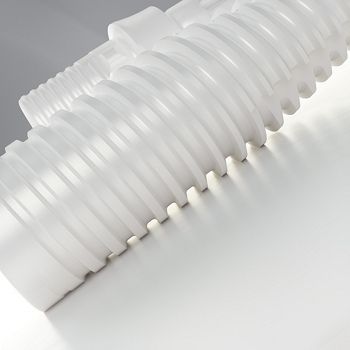

Concepto de Cuerpo Helix®

Helix® Short

Indicaciones desafiantes como la atrofia ósea vertical requieren tecnología y diseño de implantes avanzados, técnicas quirúrgicas eficientes y opciones protésicas integrales, como alternativas a los procedimientos de generación de hueso.

Cumpla con las expectativas del paciente y aumente las tasas de aceptación del tratamiento utilizando protocolos sencillos y opciones protésicas versátiles, como las que se encuentran con Neodent® Helix Short.

Solución para Atrofia Vertical

Amplia gama de longitudes: de 4 mm a 8,5 mm

Superficie Acqua

Cuello Transmucoso